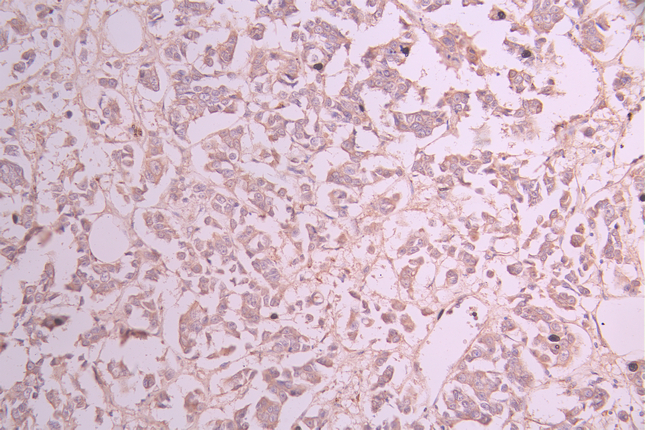

IHC image of CSB-RA244970A0HU diluted at 1:100 and staining in paraffin-embedded human stomach tissue performed on a Leica BondTM system. After dewaxing and hydration, antigen retrieval was mediated by high pressure in a citrate buffer (pH 6.0). Section was blocked with 10% normal goat serum 30min at RT. Then primary antibody (1% BSA) was incubated at 4°C overnight. The primary is detected by a Goat anti-rabbit polymer IgG labeled by HRP and visualized using 0.05% DAB.